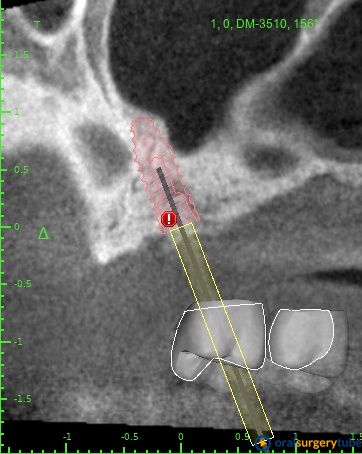

Mi plan A sería: Jugando con la cirugía guiada me cabría un implante mesial de 4x8,5 y uno pterigoideo de 3,5x10, éste en hueso nativo 100% pero con la anatomía justita. Tengo dudas si jugar en ambos lechos usar las fresas Versha para ganar algo más de altura en el mesial y mejor condensación del lecho en ambos... O no liarla y dejarlo así como os digo sin versha.